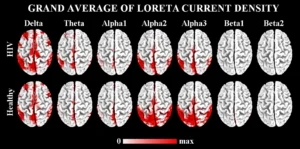

Sorgenti Corticali Anomale dei Ritmi EEG a Riposo, in Soggetti HIV Positivi, al Trattamento Naïve

Lo studio propone un metodo basato sullo Z-score per individuare...